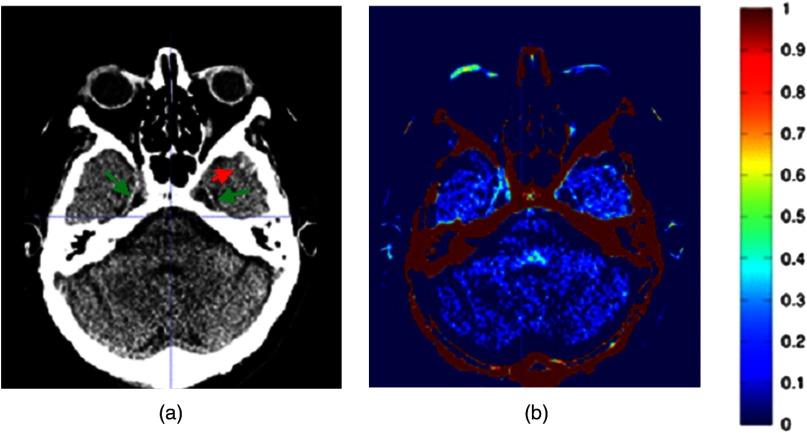

Computed tomography is a standard diagnostic imaging technique for patients with traumatic brain injury (TBI). A limitation is the poor-to-moderate sensitivity for small traumatic hemorrhages. A pilot study using an automatic method to detect hemorrhages [Formula: see text] in diameter in patients with TBI is presented. We have created an average image from 30 normal noncontrast CT scans that were automatically aligned using deformable image registration as implemented in Elastix software. Subsequently, the average image was aligned to the scans of TBI patients, and the hemorrhages were detected by a voxelwise subtraction of the average image from the CT scans of nine TBI patients. An experienced neuroradiologist and a radiologist in training assessed the presence of hemorrhages in the final images and determined the false positives and false negatives. The 9 CT scans contained 67 small haemorrhages, of which 97% was correctly detected by our system. The neuroradiologist detected three false positives, and the radiologist in training found two false positives. For one patient, our method showed a hemorrhagic contusion that was originally missed. Comparing individual CT scans with a computed average may assist the physicians in detecting small traumatic hemorrhages in patients with TBI.

计算机断层扫描是创伤性脑损伤(TBI)患者的标准诊断成像技术。其局限性在于对小创伤性出血的敏感性较差至中等。本文介绍了一项试点研究,该研究采用自动方法检测TBI患者直径[公式:见原文]的出血情况。我们使用Elastix软件中实现的可变形图像配准技术,从30例正常非增强CT扫描中创建了一个平均图像,并使其自动对齐。随后,将平均图像与TBI患者的扫描图像对齐,并通过对9例TBI患者的CT扫描图像与平均图像进行逐体素相减来检测出血情况。一位经验丰富的神经放射科医生和一位正在接受培训的放射科医生评估了最终图像中出血的情况,并确定了假阳性和假阴性。这9例CT扫描包含67处小出血,其中97%被我们的系统正确检测到。神经放射科医生检测到3例假阳性,正在接受培训的放射科医生发现2例假阳性。对于一名患者,我们的方法显示出一处最初被漏诊的出血性挫伤。将个体CT扫描与计算出的平均图像进行比较,可能有助于医生检测TBI患者的小创伤性出血。